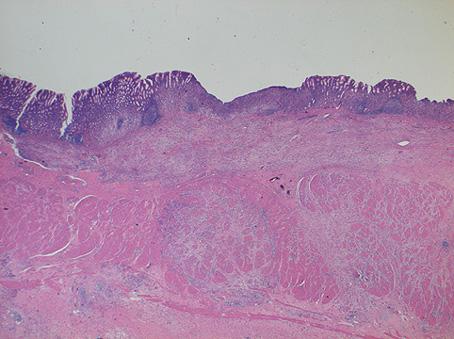

Criteria of Hist.ClassificationMalignant epithelial tumor/Adenocarcinoma

LocationStomach/Antrum

Macroscopic TypesType 3 Ulcerated type with infiltration/

Size40 -

Depth of Tumor Invasionserosa (adventitia)